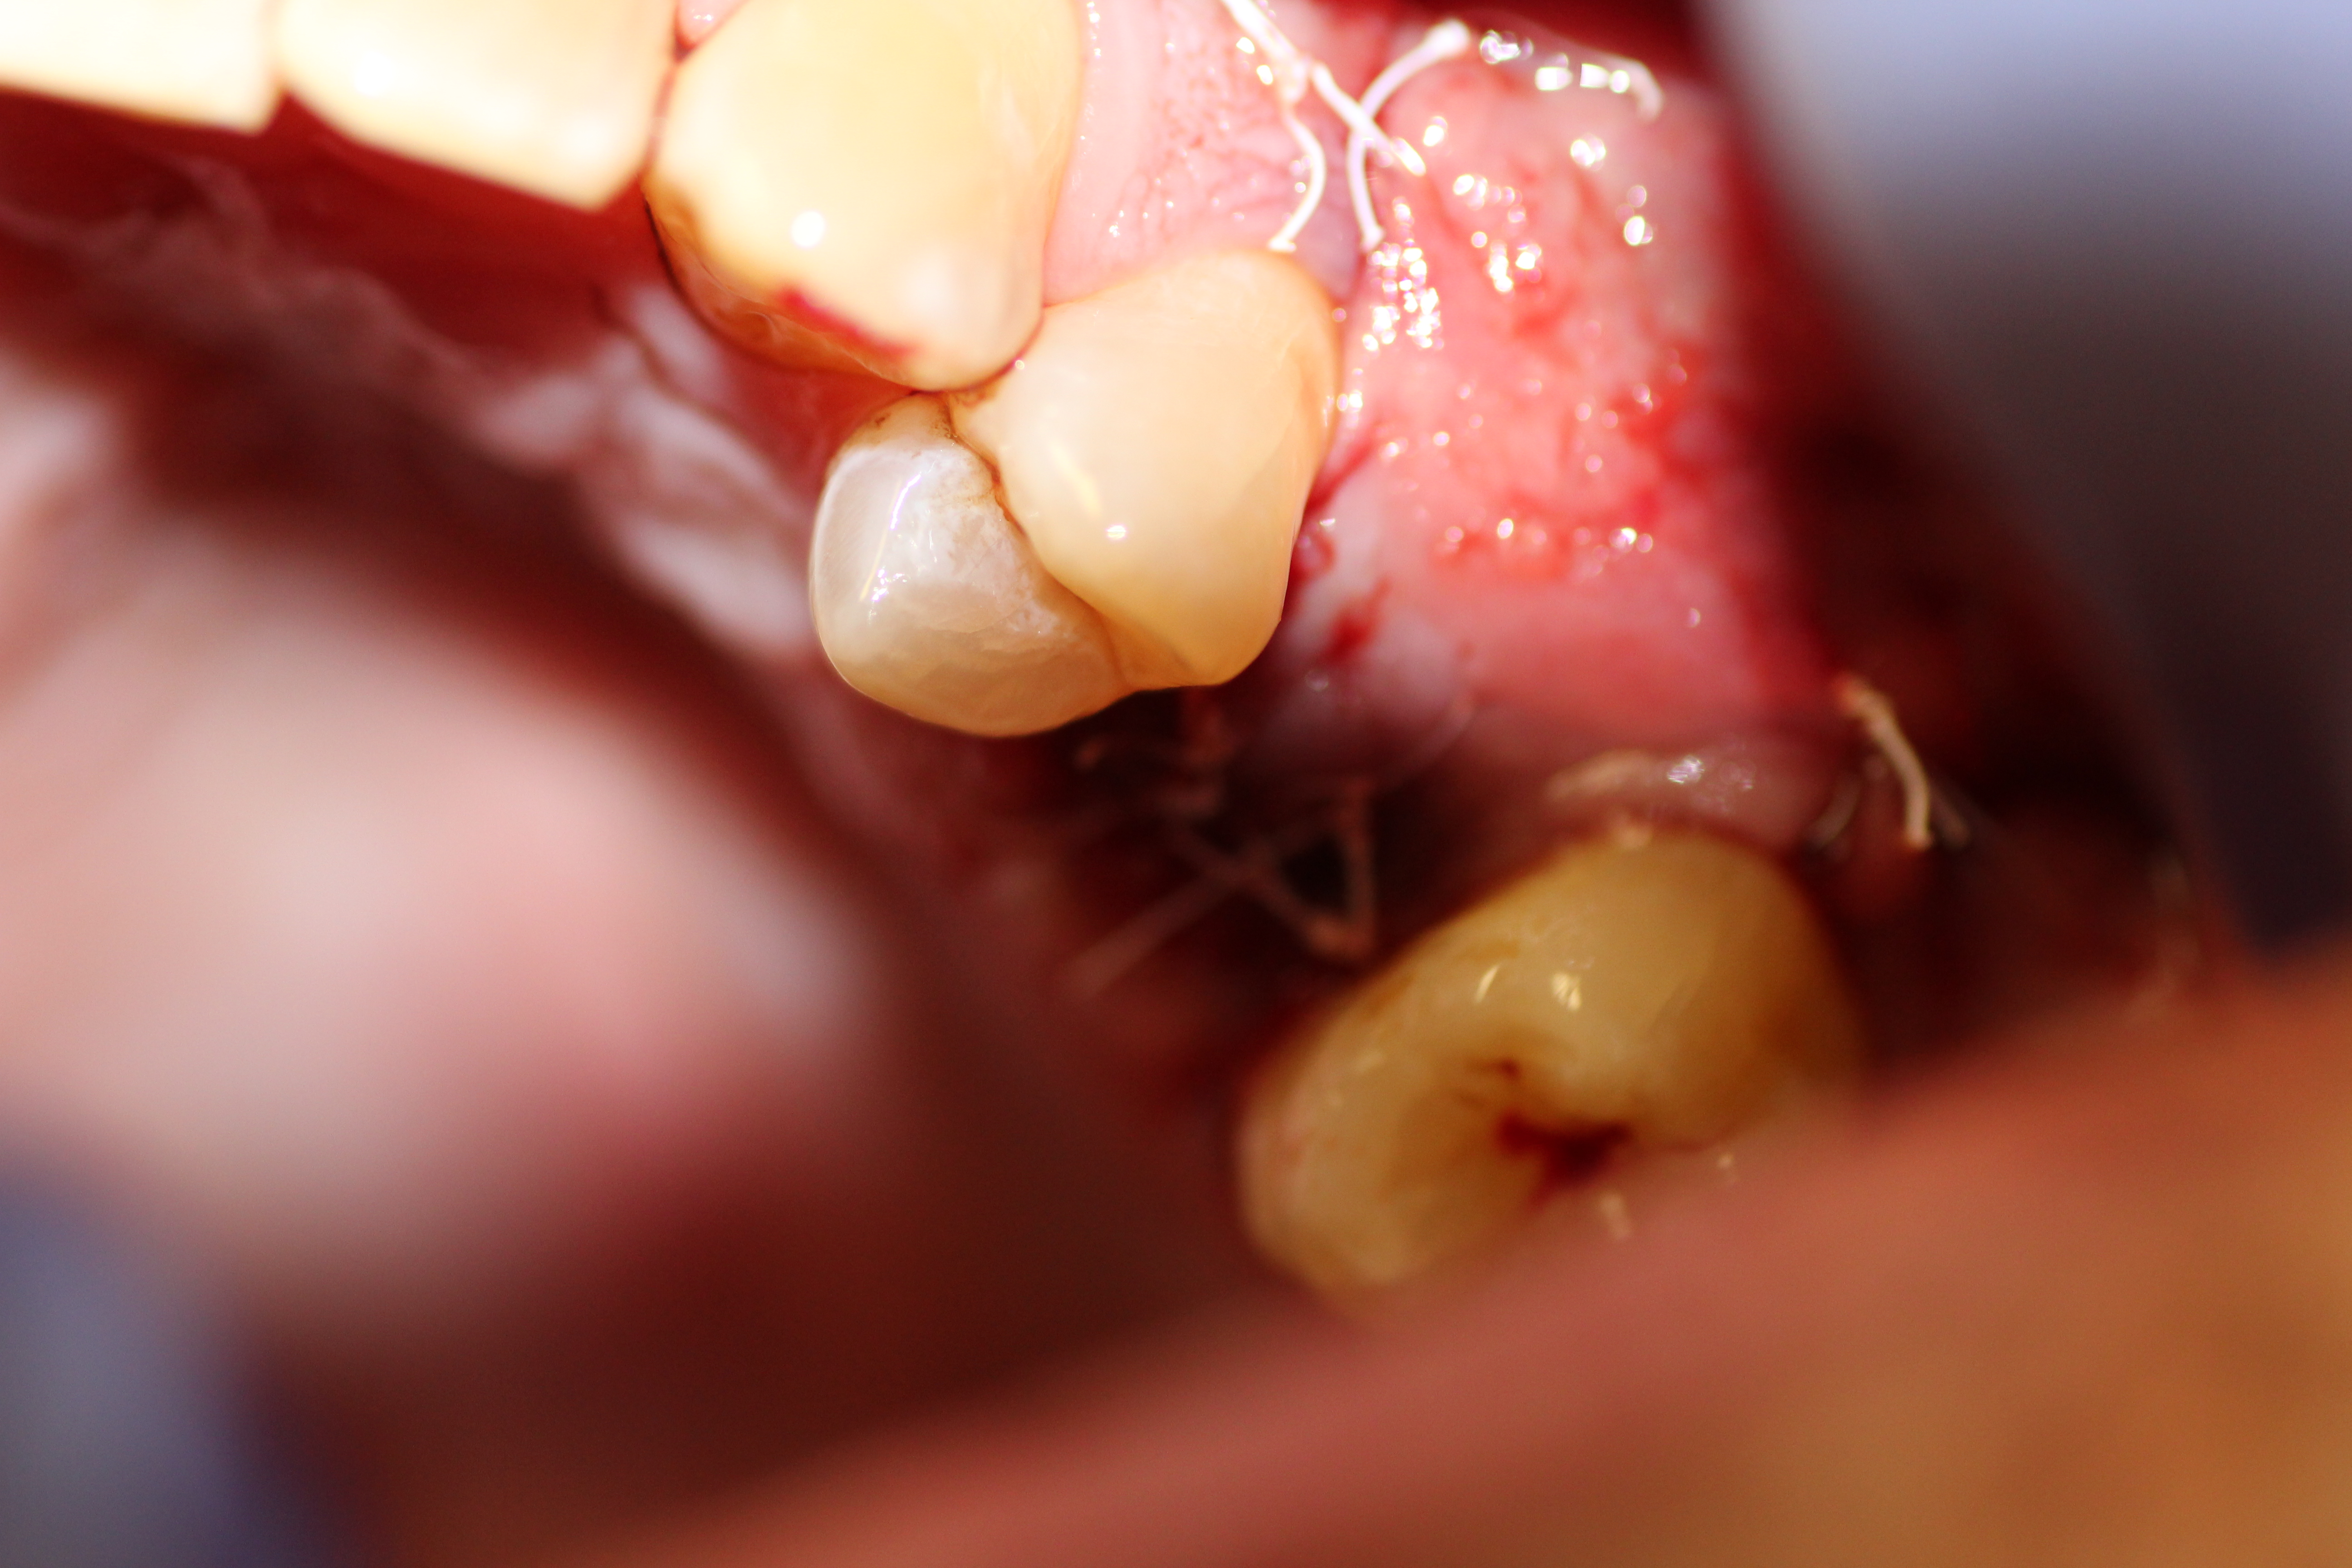

Case #2

Extraction and immediate implant placement with guided bone regeneration.

- Tooth extraction complete.

- A large bony defect on the buccal wall.